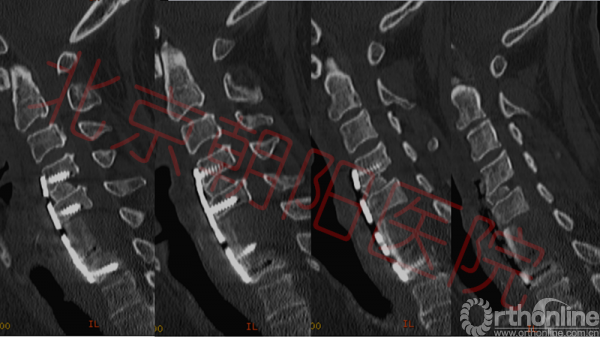

入院后常规给予患者营养神经等治疗,患者第二天出现体温升高,最高达38.5℃,同时血常规回报:白细胞12.81*10^9,中性粒细胞80.5%,淋巴细胞12.7%;ESR:80mm/h(正常值2-15);CRP:1.19ng/dl(正常值0-0.8)。降钙素原:提示基本无细菌感染或是细菌感染恢复期;考虑患者存在感染!立即给予患者头孢西丁钠抗感染治疗。复查胸椎核磁、颈椎核磁、颈椎CT(如图2,3);腰椎穿刺取脑脊液,脑脊液压力高;完善脑脊液常规、生化、免疫及结核相关检查,结合患者症状、病史、体征及辅助检查,排除肿瘤、免疫、结核、真菌感染等疾病,考虑诊断为化脓性颈椎炎,硬膜外脓肿,颈椎病,不完全性瘫痪,II型糖尿病。

图2:如图可见脊髓多节段受压,C6、C7椎体及椎间盘高信号,C6-C7椎体后方可见高密度影,C5-C8椎体前方高密度影。脊髓内可见高信号区域

图3:如图可见C6、C7椎体不同程度骨质破坏